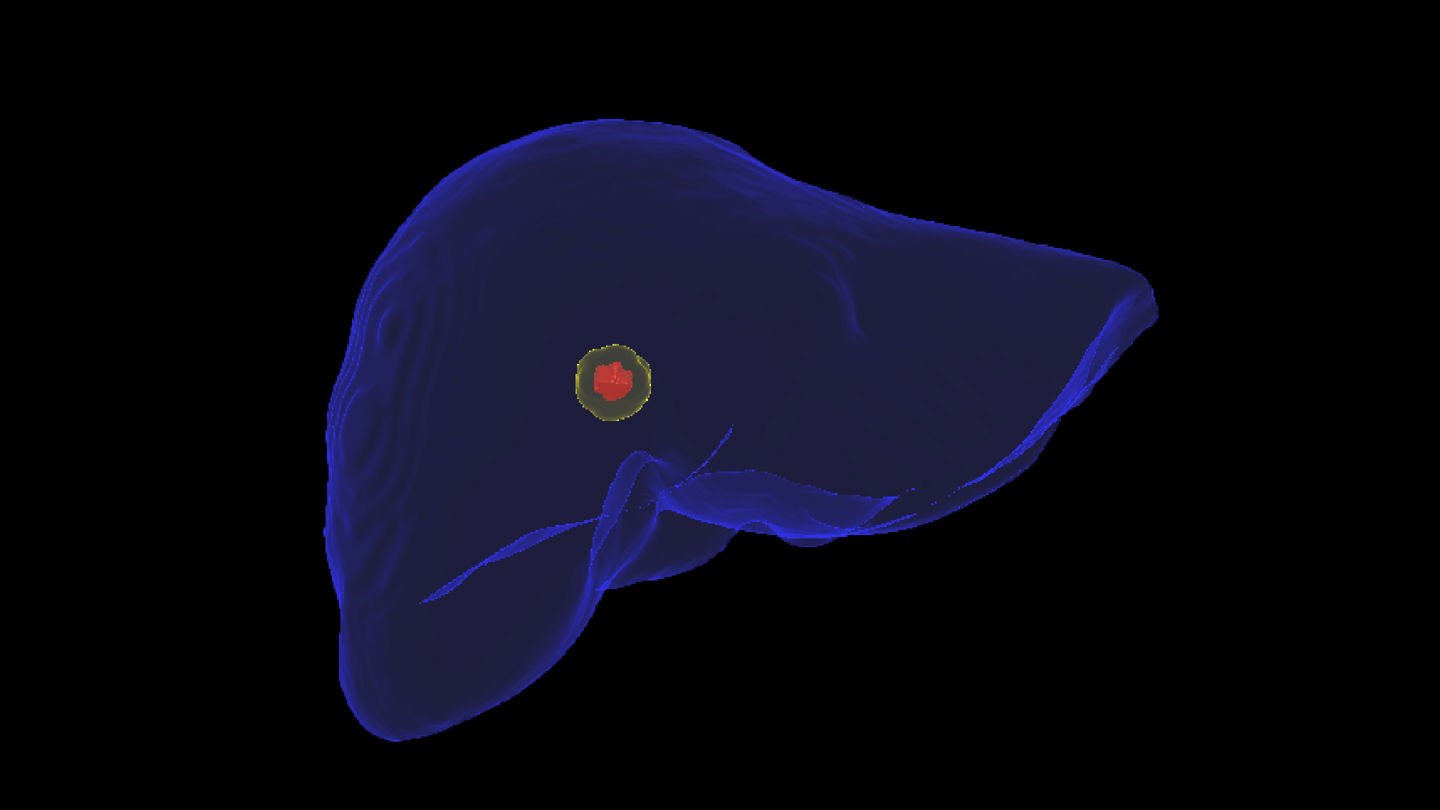

The Liver Ablation module offers tools for automatic segmentation of relevant structures. Combined with the ability to place virtual applicators and estimate the ablation zone, our software assists users to determine the optimal number of applicators and their precise placement.